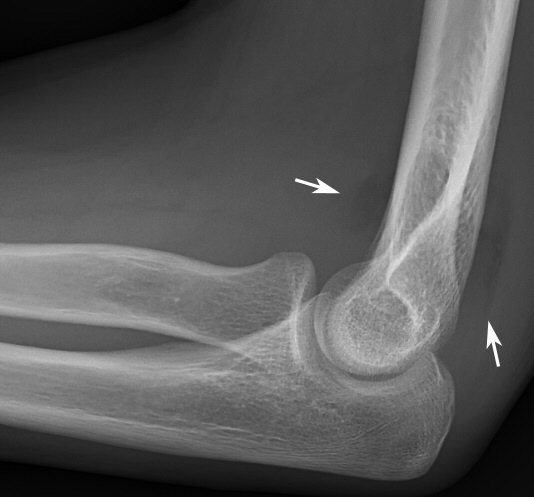

Fettkuddar anteriort och posteriort om distala humerus, antyder fraktur (vuxet skelett)